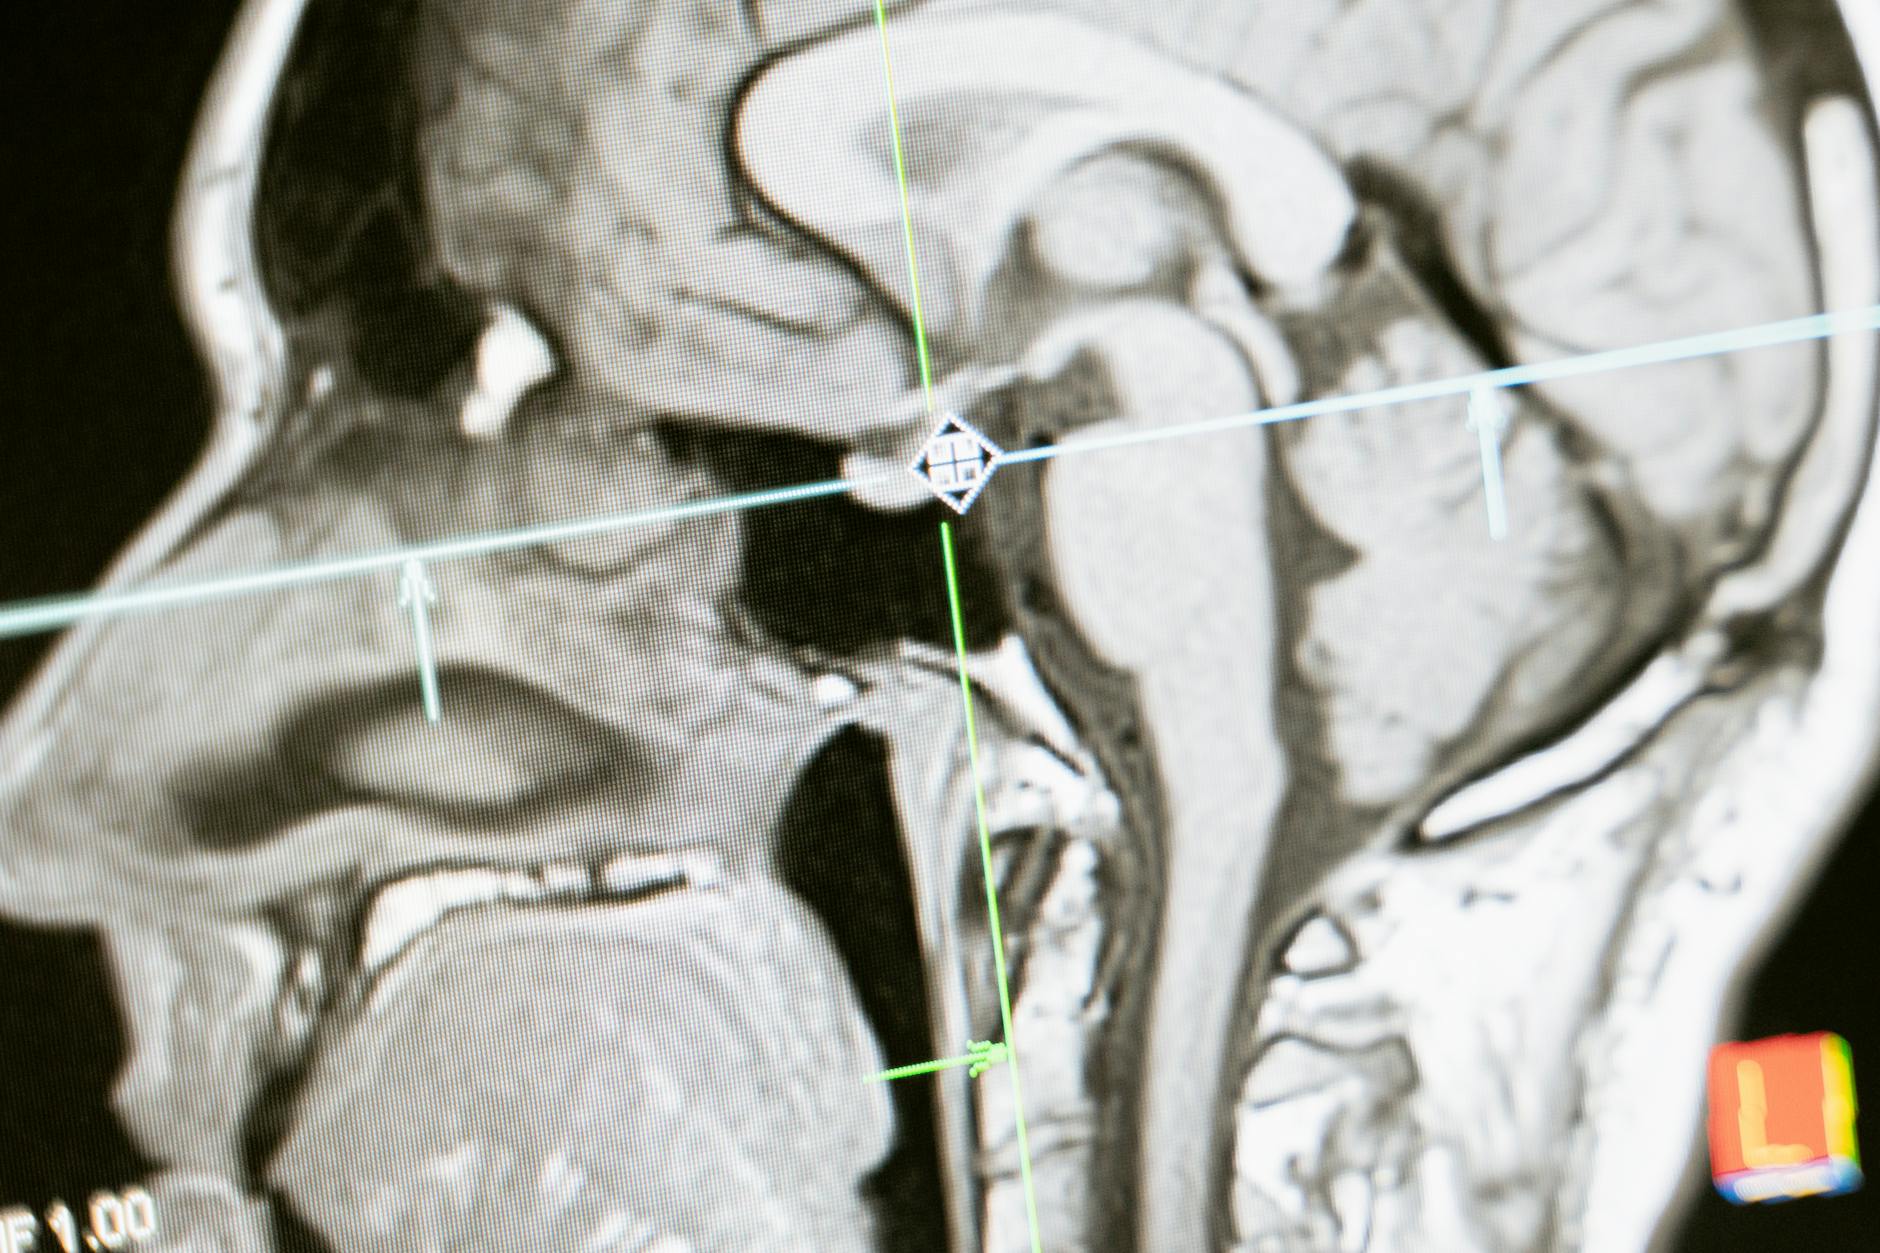

Modern neuroimaging — think fMRI and PET scans — has made it possible to watch the brain in real time. What researchers consistently see is that virtually all brain regions show activity across the course of a day. Different areas activate for different tasks: language, movement, memory, emotion, sensory processing. Even during sleep, significant portions of the brain are hard at work consolidating memories and regulating bodily functions.